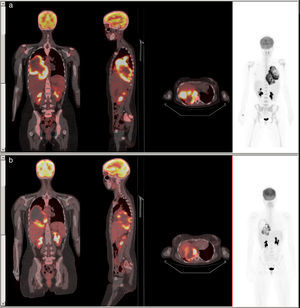

Coronal, sagittal and axial slices of PET-CT fusion imaging. (a) A large mass is observed occupying almost all the right hemithorax, with heterogeneous density and highly intense peripheral uptake (SUVmax=18.9), in contact with the parietal pleura, posterior mediastinum and right hilum. (b) Reduced metabolic uptake (SUVmax=16.8) seen after chemotherapy.

We report the case of a 22-year-old woman with no personal or family history of asbestos contact, who reported a 10-month history of right scapular pain with no other clinical complaints. Around 2 months before presenting, she developed a cyclic febrile pattern, lasting 1 week, coinciding with her menstrual cycles, along with dyspnea on exertion. She was admitted with a suspected diagnosis of pelvic inflammatory disease. Leukocytosis with significant thrombocytosis and CRP 137 were determined, and empirical treatment began with ampicillin and gentamycin, but no improvement was observed. A chest radiograph and chest-abdominal computed tomography (CT) were performed, showing a large right-sided paravertebral mass occupying almost all the ipsilateral hemithorax. The PET-CT with 18F-FDG revealed a hypermetabolic mass in the right hemithorax, suggestive of malignancy, and diffuse increased reactive uptake in the bone marrow (Fig. 1a). Biopsy found undifferentiated carcinoma in the posterior mediastinum, suggestive of right pleural mesothelioma.

Neoadjuvant chemotherapy was started, and some response was seen. Post-treatment PET-CT showed a reduced tumor size with peripheral metabolic uptake (Fig. 1b).